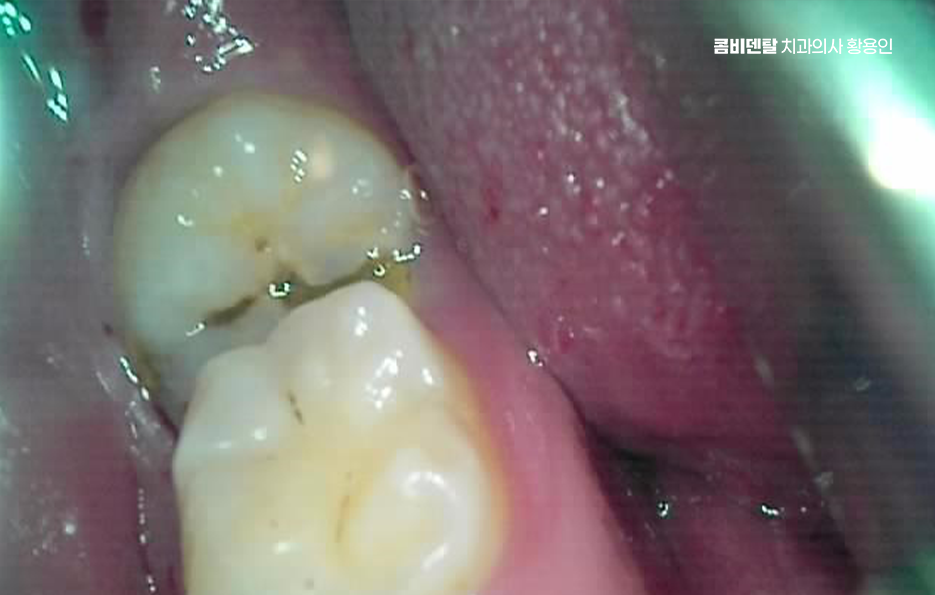

출처 아카이브 열기얼마 전부터 오른쪽 아래 어금니 근처가 묘하게 불편했어요, 처음에는 그냥 음식물이 좀 더 자주 끼는 것 같다고만 생각했는데, 어느 날부터 양치할 때 그쪽을 닦으면 묘하게 시큰한 느낌이 들었어요, 아프다고 할 정도는 아닌데 묘하게 예민하고, 시린 듯도 하고, 찜찜한 기분이 남아서 괜히 그쪽은 피해서 양치하게 되고, 그러다 보니까 오히려 더 불결하게 관리된 게 아닐까 싶은 걱정도 들기 시작했어요, 그렇게 결국 알게 된 사실은 사랑니에 충치가 생겼고, 그 사랑니 바로 앞에 있는 어금니까지 영향을 받아 충치가 함께 진행되었어요. 결국 이렇게 문제가 생기고 나니까 진작 사랑니를 뽑을 걸 하는 후회가 한꺼번에 밀려왔어요 왜 하필 그 끝에 있는 사랑니 때문에 앞에 있는 어금니까지 같이 망가졌을까, 그 어금니는 평생 써야 하는데, 이미 위치 자체가 안 좋은 사랑니 때문에 멀쩡한 어금니까지 문제가 되었다는게 안타까웠어요

다시 말해 사랑니가 문제를 일으키는 건 워낙 흔한 일이지만 사랑니 하나만 문제를 일으키는 게 아니라, 그 옆 어금니까지 같이 충치가 생기는 경우도 생각보다 많은데 특히 아래쪽 사랑니가 옆으로 누워 있는 경우에는 그 앞 어금니와 밀착돼 있어서 둘 사이가 잘 닦이지 않고 음식물이 잘 끼기 쉬운 구조라고 할 수 있었어요.

이런 사랑니는 앞 어금니와 비정상적인 접촉을 하게 되면서 음식물이 계속 끼고 세균이 쌓이게 되며 아무리 양치질을 잘한다고 해도 물리적으로 칫솔이 닿기 어려운 구조라서 결국 충치나 염증으로 이어지는 경우가 많은 거예요

문제는 여기서 끝나지 않고 누운 사랑니와 앞 어금니 사이에 충치가 동시에 생기는 경우는 치료가 더 복잡해질 수 밖에 없는데 왜냐면 사랑니가 옆으로 누워 있으니까 앞 어금니 뒷면에 생긴 충치를 제대로 보기도 어렵고, 치료 기구가 들어갈 공간도 부족해져서 충치 치료가 더 까다로워지는 것이며 특히 앞 어금니 뒷면에 생긴 충치는 환자도 자각하기 어렵고, 진단 시기도 늦어지는 경우가 많아서 이미 신경까지 손상됐거나 신경치료가 필요한 상태로 발견되는 일도 많이 있었어요